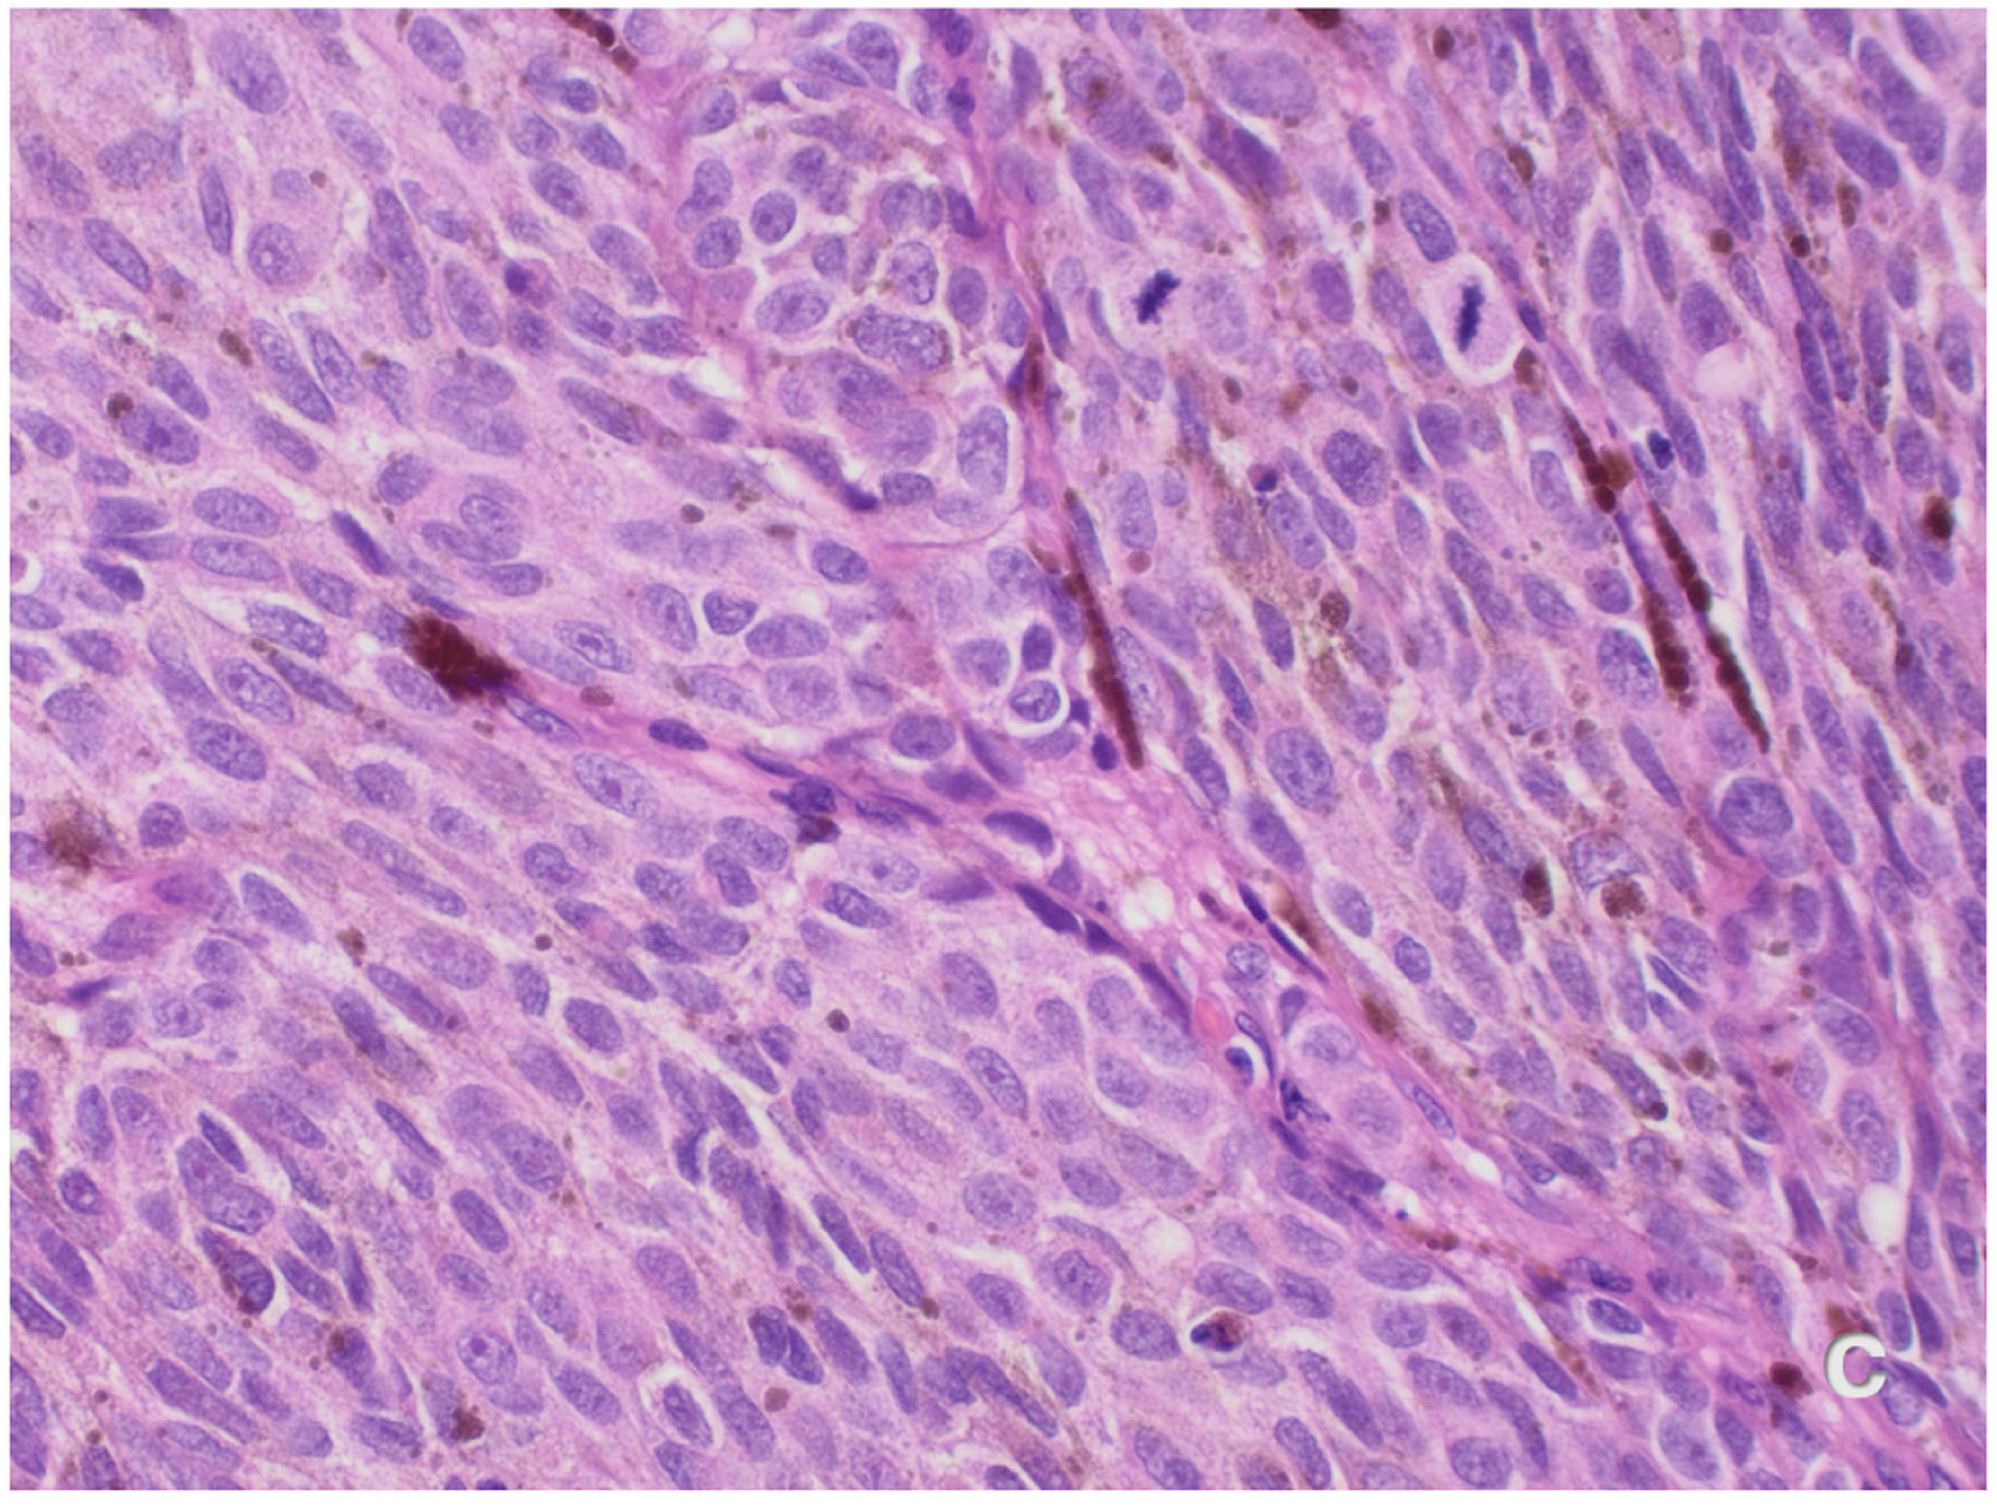

Case Presentation